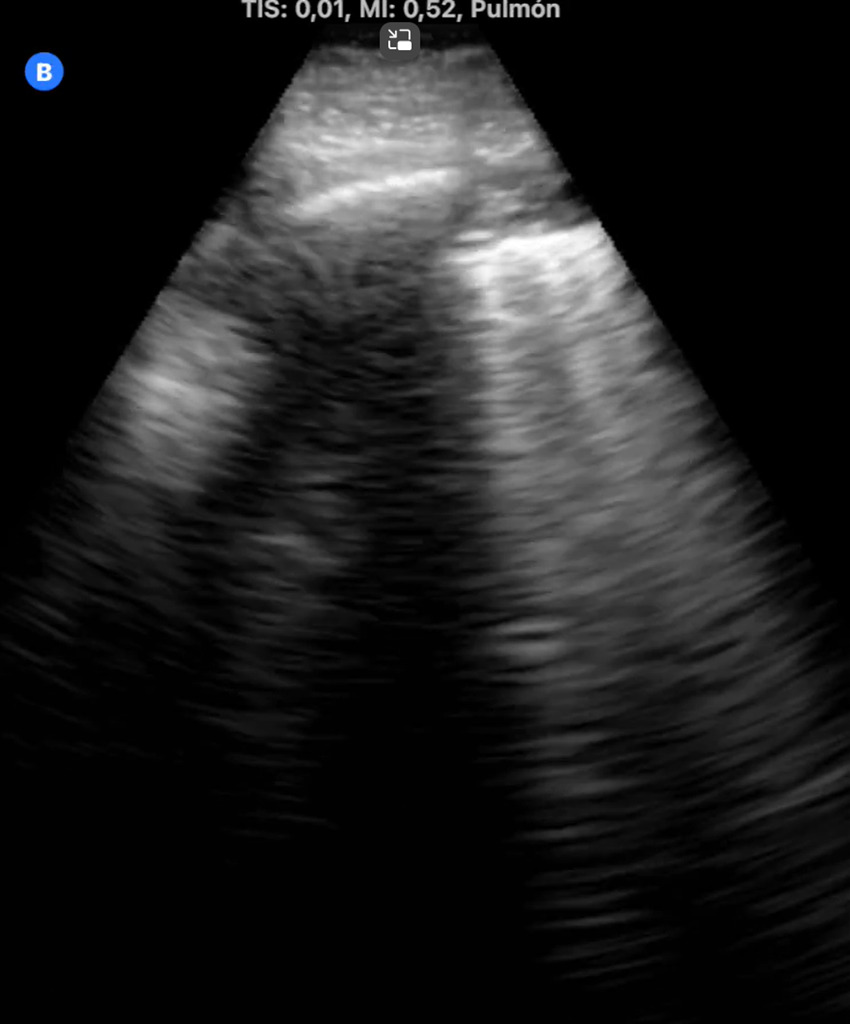

La ecografía pulmonar nos permite aumentar la capacidad diagnóstica y resolutiva, con gran rapidez y gran número de situaciones clínicas, disminuyendo el nivel de incertidumbre. Nos ayuda a tomar decisiones y ofrecer un mejor cuidado a los pacientes. Permite evaluar la extensión y gravedad de la enfermedad, así como monitorizar la progresión y evaluar las complicaciones.

Además, ayudándonos de la ecografía pulmonar, hemos podido diagnosticar diferentes patologías pulmonares intersticiales como neumonitis intersticial por metotrexate, neumopatía intersticial tipo NINE y síndrome alveolo intersticial.

La ecografía es una herramienta valiosa en la evaluación y manejo de patologías pulmonares intersticiales, proporcionando información clave que puede influir en el tratamiento y pronóstico del paciente.